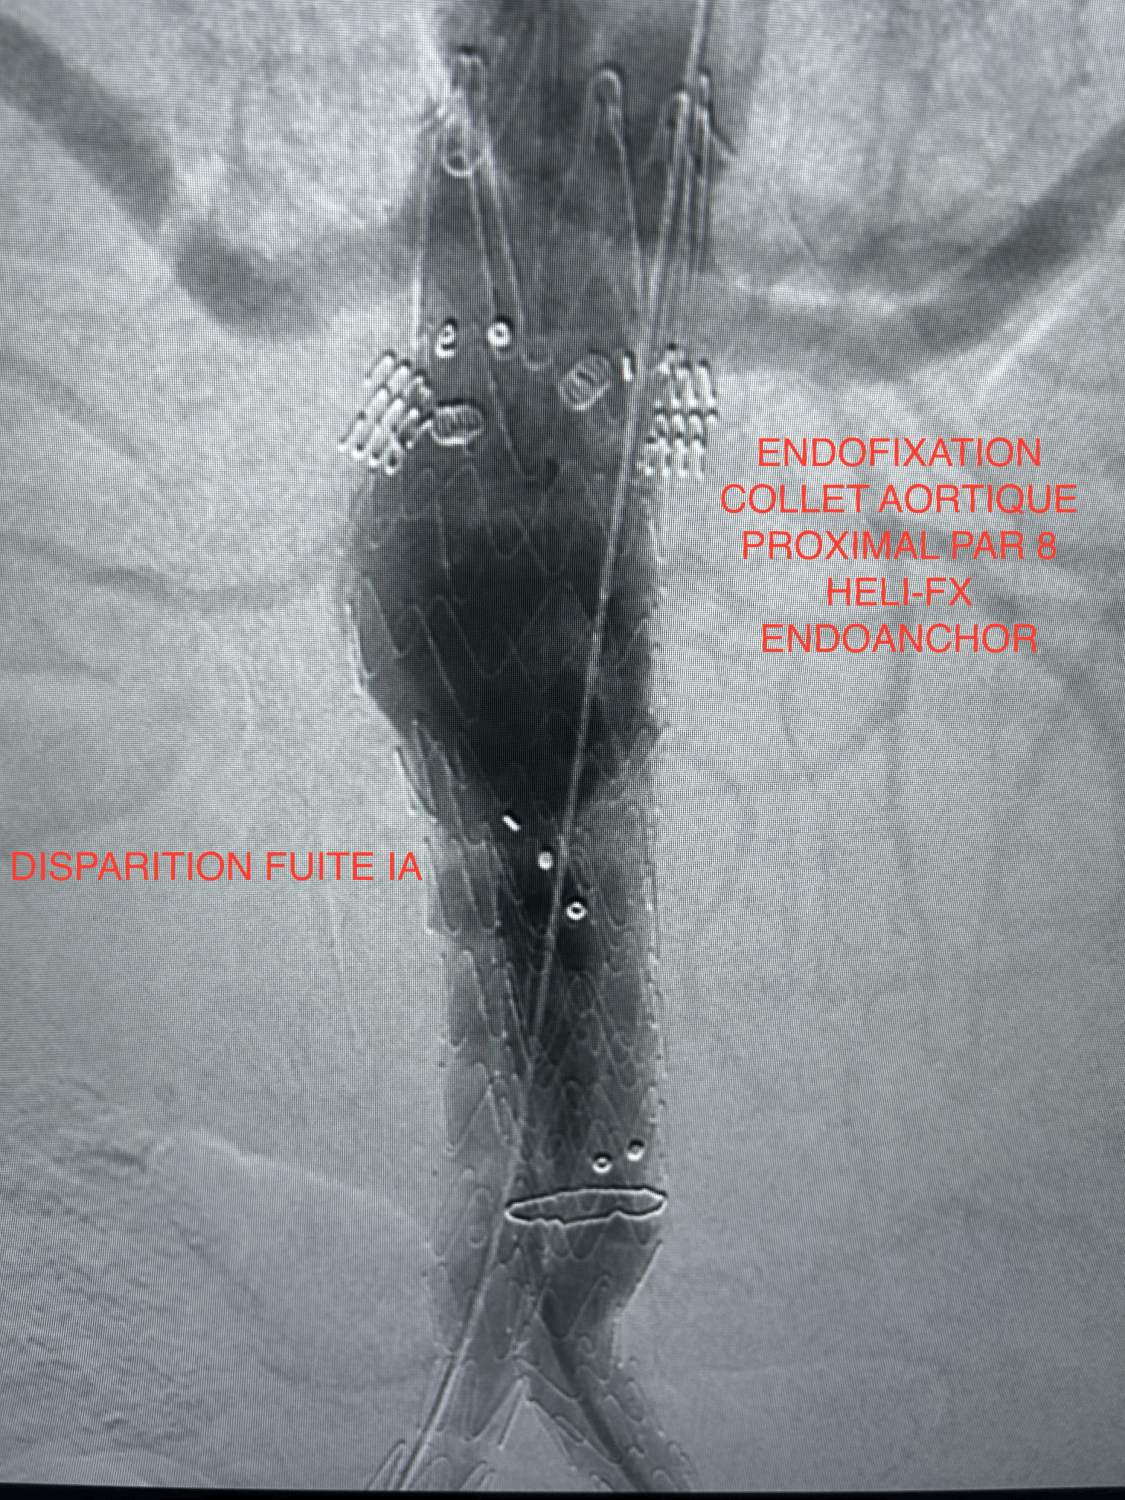

Fuite de type IA persistante au contrôle artériographique per-opératoire après inflation prolongée du collet aortique proximal et de la totalité de l'endoprothèse aortique à l'aide d'un ballon ENDURANT. Pas de possibilité de mettre en place une CUFF aortique plus proximale.

Mise en place de 8 Heli-FX EndoAnchor en "STOCK", mises en "croix", au niveau du collet aortique sous-rénal, juste en aval de l'artère rénale gauche.

Disparition immédiate et complète de la fuite de type IA sans nouvelle inflation du corps de l'endoprothèse.